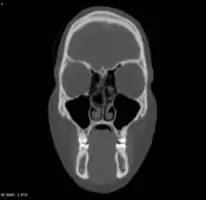

Bilateral concha bullosa, larger on the left -